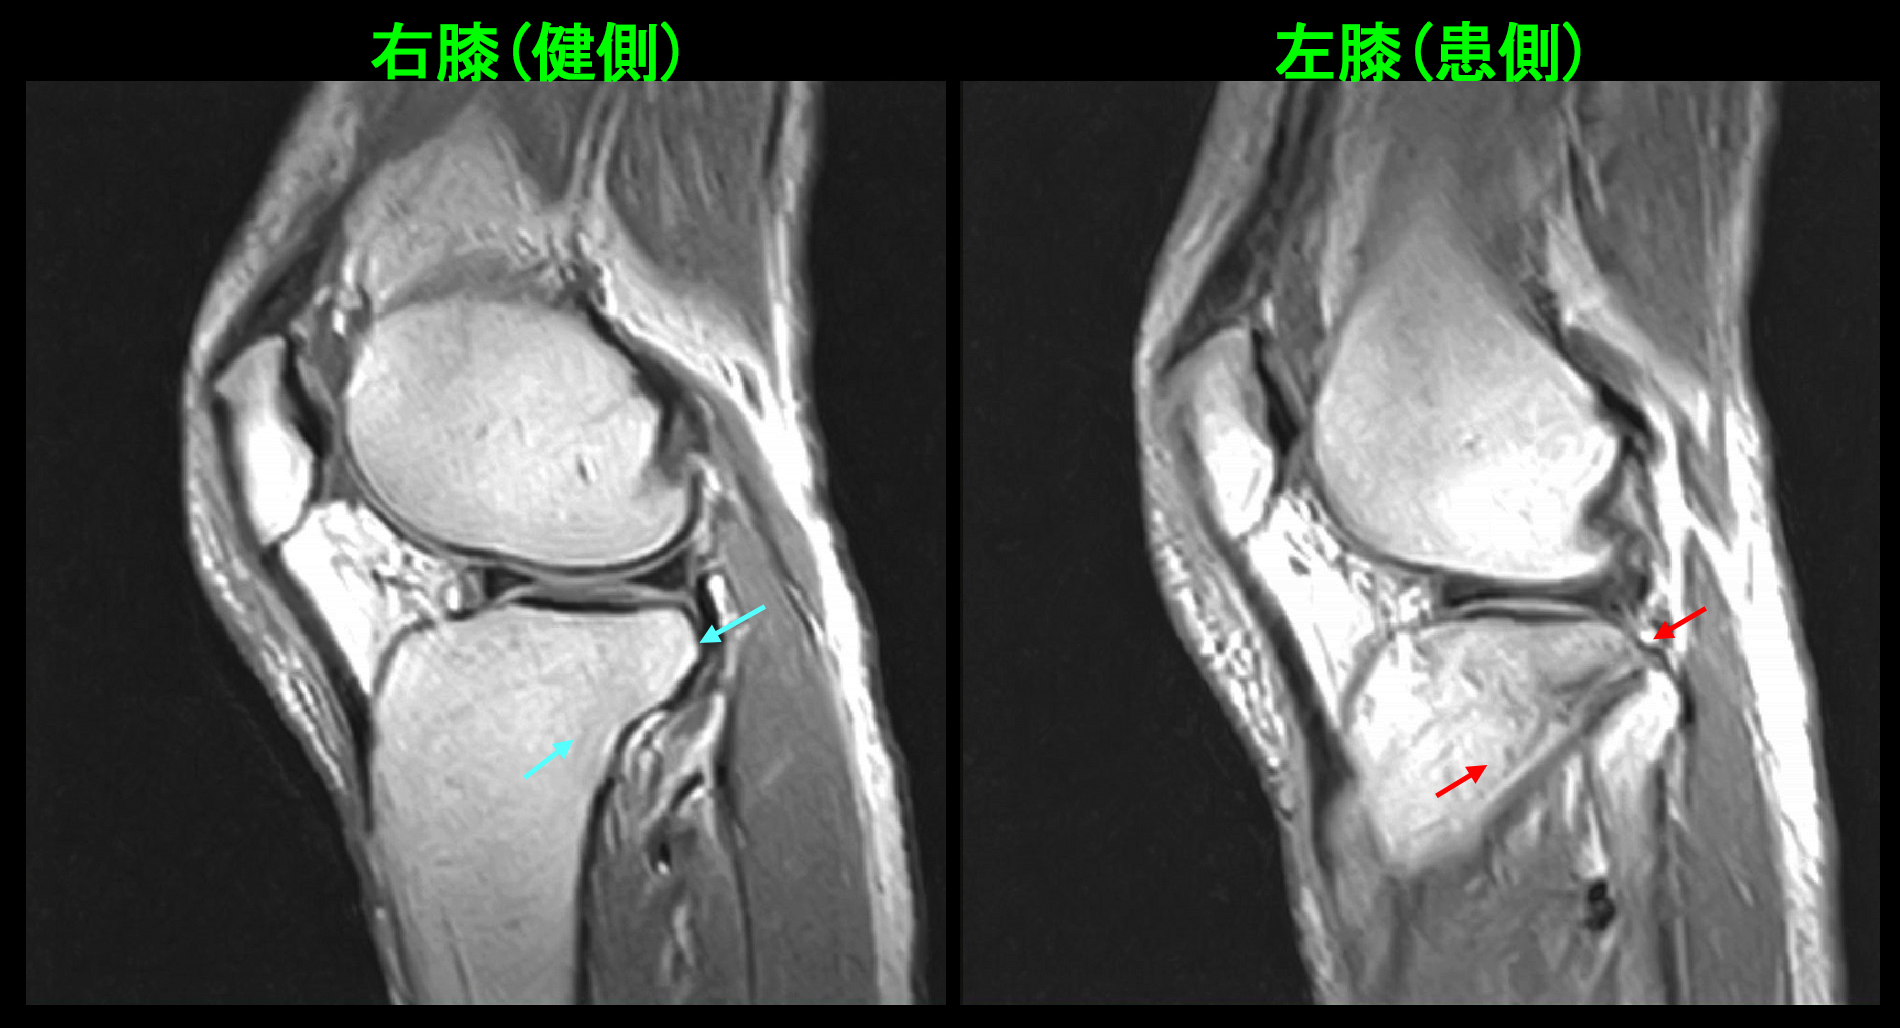

74才女 MR1.jpg

T1というMRI条件での冠状断(前後像)となりますが、赤矢印が本来白い骨が黒くなっており、骨の損傷を示します。骨折です。

74才女 MR2.jpg

T1矢状断(側面像)でも赤矢印が骨折所見です。骨折(骨が損傷)していても、当初はダンスも可能であったのです。私は4週間の安静を指示しましたが、Mさんは12月10日(4週後)にクリスマスのダンス発表会があり、ドレスも購入してしまったと言っていました。私は、「諦めた方が無難ですが、私は私の判断を強制しません。気合いと根性で頑張れそうだったらやってもいいのではないですか。Mさん次第です。」と述べました。Mさんはダンス発表会にも出場して、問題なかったと教えてくれました。